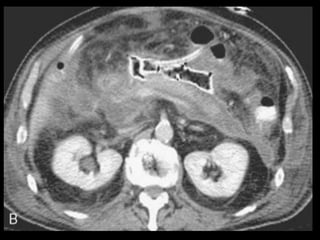

PANCREATITE AGUDA GRAVE

Ocorre em 20-30% dos pacientes com PA;

Caracteriza-se por evolução protraída, insuficiência

de múltiplos órgãos e necrose pancreática;

Necrose pode ser difusa ou esparsa, superficial ou

profunda, e pode afetar qualquer parte do

pâncreas;

A necrose ocorre logo de início, em 24-48 horas,

ela permanece estável, com raras exceções.

Os resultados TC são melhores indicadores

prognósticos que sistemas de escores numéricos,

devido a sua maior sensibilidade e especificidade.

A administração de contraste IV é essencial,

especialmente em pacientes com PA grave, para

visualizar o pâncreas, diferenciar a glândula de

coleções líquidas adjacentes e do tecido

inflamatório peripancreático e demonstrar a

necrose pancreática.

Áreas focais ou difusas de realce diminuídas ou

ausente à TC contrastada dinâmica constituem

áreas de isquemia ou necrose.

TC tem precisão geral de 87% com S e E de 100%

para necrose extensa e 50% com áreas menores.